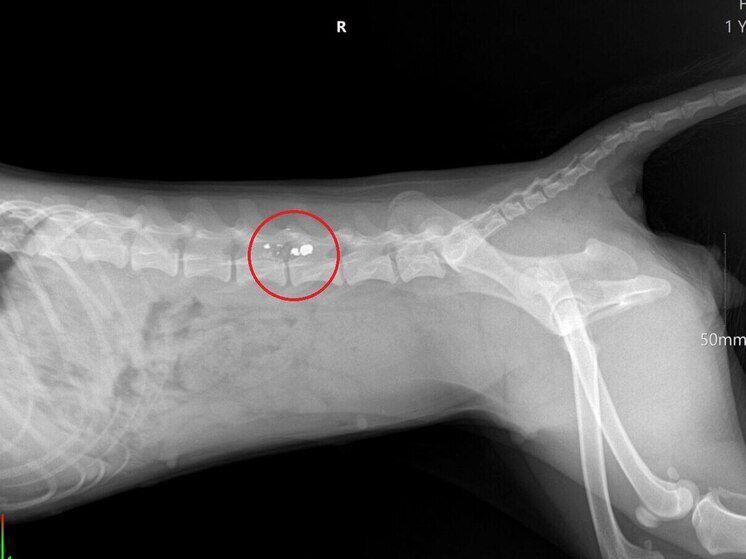

Хозяева оперативно доставили раненое животное в ветеринарную клинику. Врачи диагностировали у собаки серьезные травмы, приведшие к параличу тазовых конечностей.